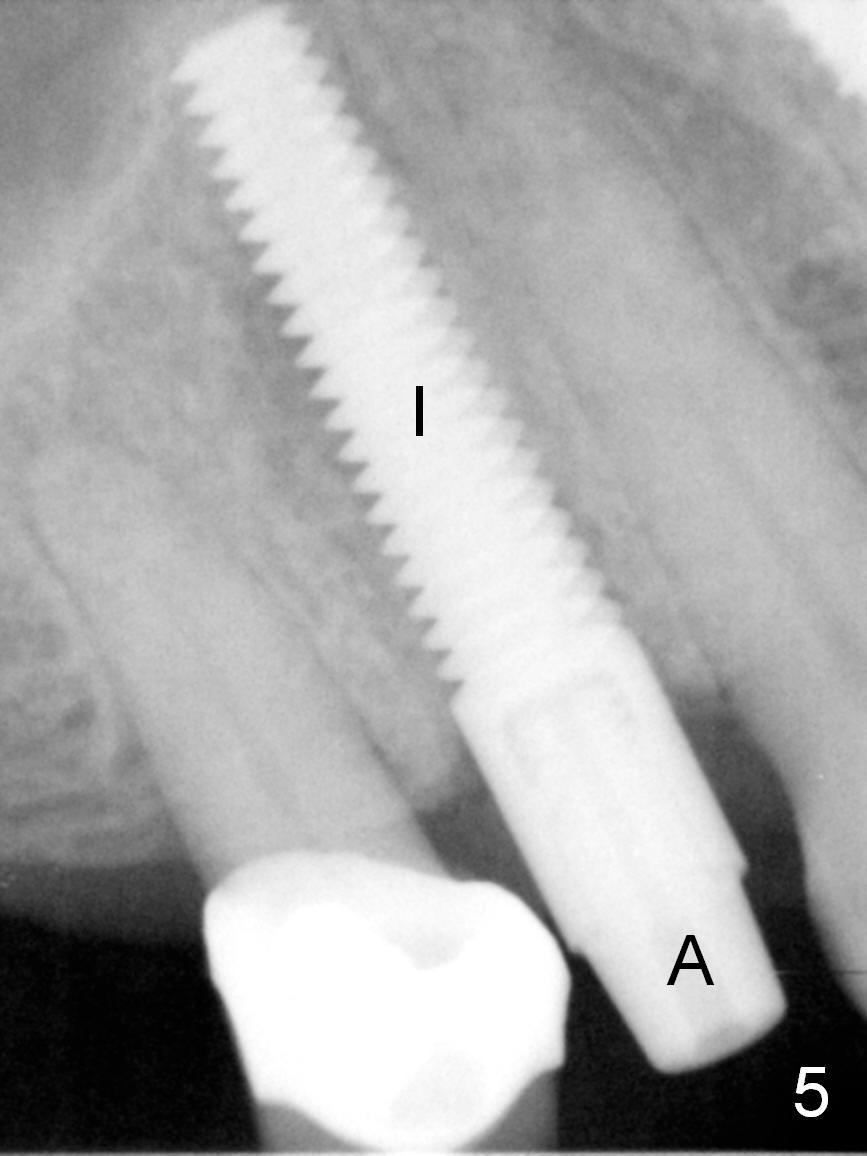

After long discussion, she agrees with extraction and immediate implant.  After the extraction, granulation tissue is removed.  There is buccal apical fenestration.  The socket is treated with Metronidazole.  The socket depth is 17 mm, while osteotomy depth is 20 mm (Fig.4).  A 4x20 mm tissue-level implant is placed with primary stability (Fig.5,6 I).  A short abutment (A) is placed immediately for an immediate provisional.  The buccal gap is filled with Osteogen plug.  There is no crestal bone loss 3 months postop (Fig.7).  The provisional stays in place with occlusal perforation.  The gingiva is healthy 5.5 months post cementation (Fig.8).